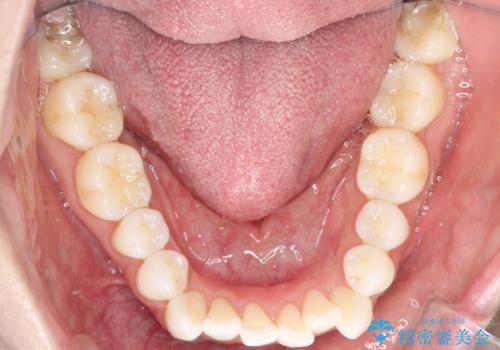

- 患者さんは「口元を引っ込めたい」「八重歯をきれいにしたい」とのご希望で来院されました。診察の結果、上下の前歯が前方に傾斜し、口元がやや突出して見える状態でした。加えて、上顎には八重歯があり、歯列のスペース不足も確認されました。

歯並びと横顔のバランスを整えるためには、前歯を後方に移動させるスペースの確保が必要です。そのため、上下左右の第一小臼歯(合計4本)を抜歯し、ワイヤー矯正で前歯の突出感と叢生(がたつき)を同時に改善する治療計画を立てました。歯を抜くことに抵抗がある方も多いですが、口元の印象を変えるためには非常に効果的な方法です。

上下左右の小臼歯を抜歯後、ワイヤー矯正装置を装着し、全体のバランスを見ながら歯を移動させていきました。特に前歯の後方移動では、抜歯スペースを活かして口元を内側に下げることに重点を置きました。また、八重歯も時間をかけて丁寧に整列させ、左右の正中(真ん中の位置)もぴったりと揃えることができました。

治療期間は約2年で、歯並びだけでなく横顔の印象も大きく改善されました。治療後には「口元がすっきりして笑顔に自信が持てるようになった」とのお声をいただきました。現在は後戻りを防ぐため、保定装置(リテーナー)を使用しながら経過観察中です。ワイヤー矯正は審美性と機能性を両立できる有効な選択肢の一つです。